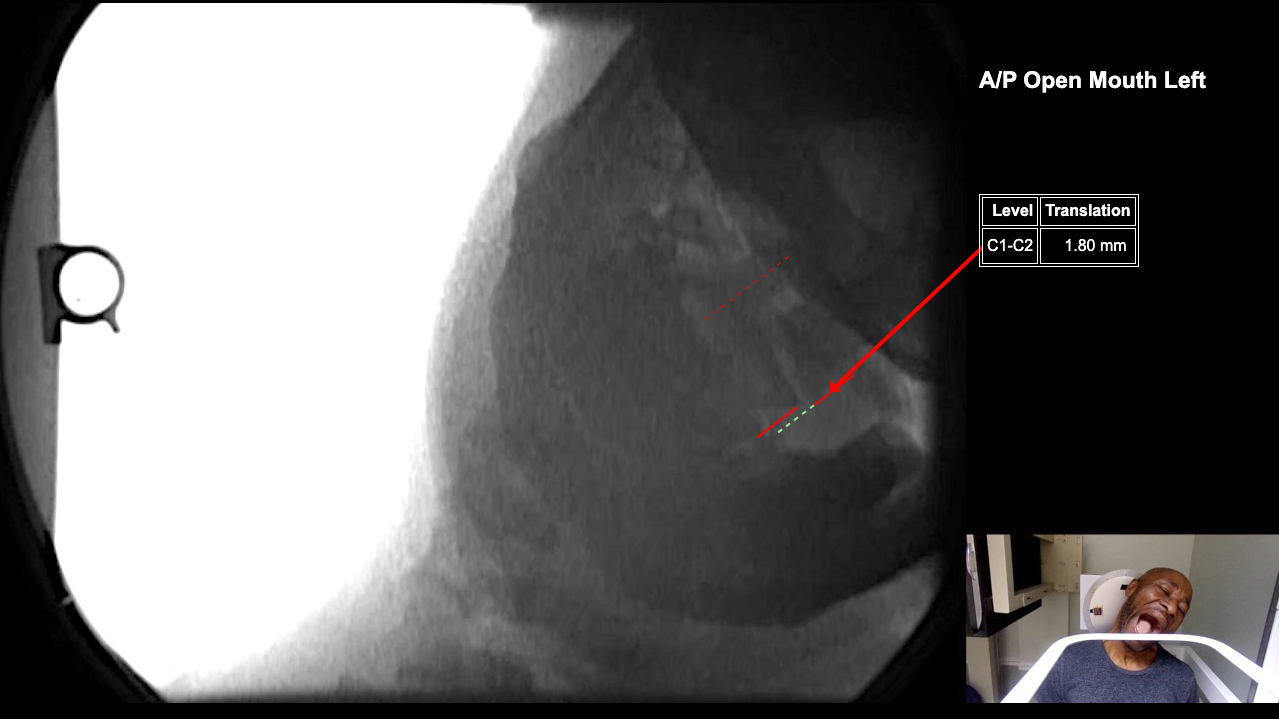

Image Name Image Type Image